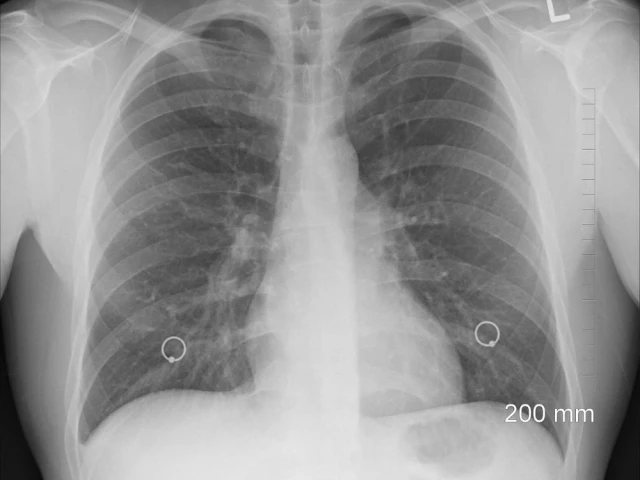

It works by addressing the underlying causes of the inherited disease — which wreaks havoc on the lungs and digestive system — rather than its symptoms.

Some 100,000 people worldwide are estimated to suffer from cystic fibrosis, in which sticky mucus builds up in the lungs, digestive tract and other parts of the body.